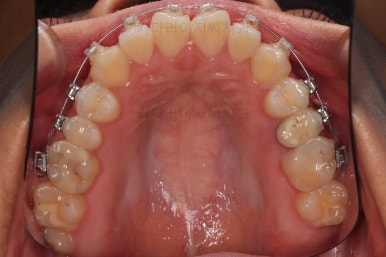

부산치아교정잘하는곳 키다리아저씨치과에서 사용한 장치는 엠파워라고 하는 자가결찰 장치인데요.

이번 환자분은 윗니는 세라믹, 아랫니는 메탈로 선택을 하셨습니다.

웃을 때 더 많이 보이는 부분은 좀 더 심미적인 세라믹으로 하고, 아랫니는 메탈도 상관없다고 하여 조합해서 사용했는데요.

동일한 회사의 동일한 규격의 장치라 혼용해서 써도 무방합니다.

장치 부착한지 얼마 안되어 치열은 매우 고르게 되었는데요.

치료 목표는 그것 뿐만 아니라 입을 조금이라도 넣고, 앞니 각도도 개선해야 되었으므로 사랑니는 모두 뽑아내고 미니스크류를 활용해서 뒤로 뒤로 밀어넣습니다.